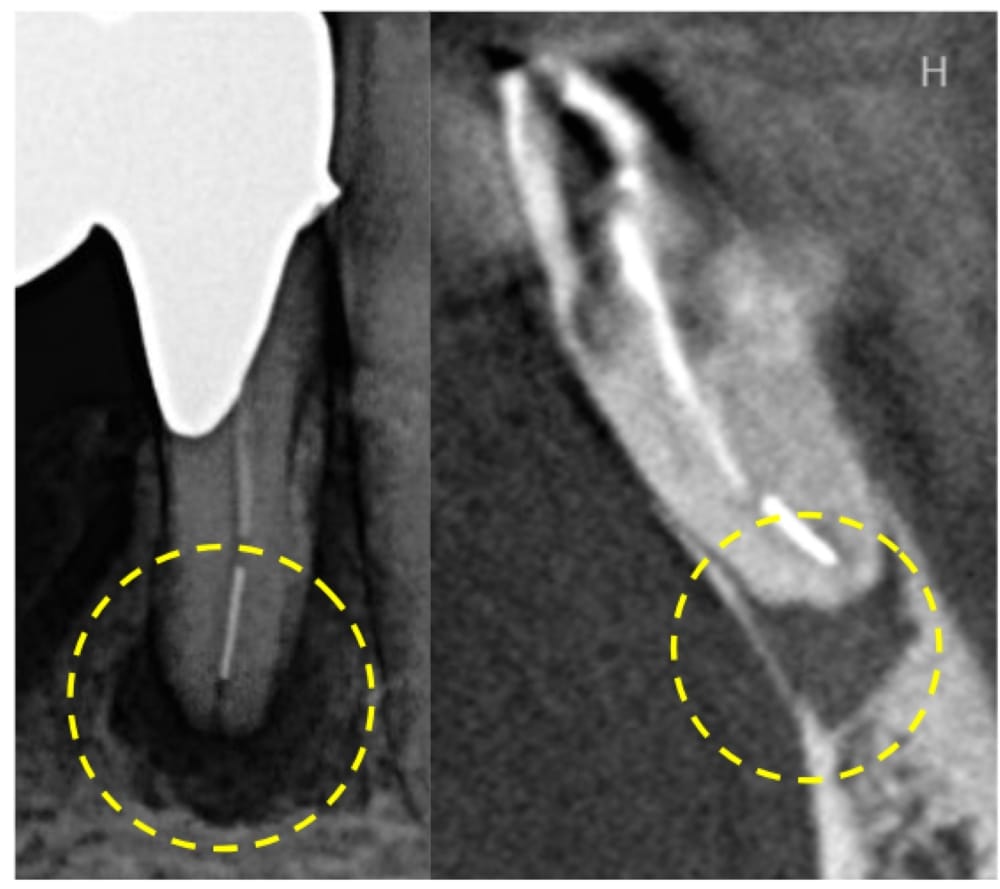

下顎前歯の根の先に、はっきりと黒い影(骨吸収像)が認められます。腫れや痛みの症状もあることから、根尖性歯周炎と診断しました。

レントゲン画像では、根管内に白い不透過像も認められ、形状からおそらく破折ファイルと推測される状態でした。

根の先端部分に破折ファイルの断端が確認できたため、除去を試みました。

除去した破折ファイルの写真です。レントゲン画像ではある程度の長さがあるように見えますが、実際に除去したファイルはおよそ2.5mm程度でした。

根管内を清掃すると、根の先端部分が大きく開いている状態でした。通常のガッタパーチャポイントを使用した根管充填では緊密な封鎖が困難なため、MTAセメントを使用して根尖部分を封鎖しました(写真は、MTAセメントを充填した直後)。

術前にはっきり写っていた根の先の黒い影は術後6ヶ月でほぼ消失しており、骨の回復が認められます。患者様の症状も痛み・腫れともに完全に消え、良好な状態でした。根の問題は解決したため、このまま最終補綴(セラミックのブリッジ)へ移行することになりました。